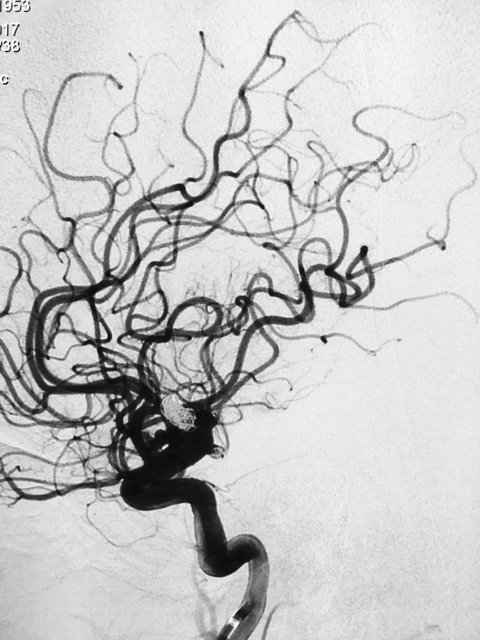

SNA. 76 anos. Durante investigação ambulatorial de cefaléia e tremor nas mãos foi realizado Angiotomografia de crânio evidenciando aneurisma incidental em topo da artéria carótida interna esquerda. Foi realizado Angiografia Cerebral diagnóstica para programação adequada do tipo de abordagem cirúrgica, neste exame confirmou a presença deste aneurisma sacular de contornos irregulares, com orientação superior e anterior, medindo 7,0 x 4,0mm com colo estimado de 4,5mm.

Diante da localização do aneurisma ( intradural ) foi indicado o procedimento terapêutico endovascular. Desde então se programou abordagem com uso de neurostent e molas em virtude da largura do colo do aneurisma. A discussão maior foi em relação ao posicionamento deste stent, direcionando para segmento A1 da artéria cerebral anterior ou segmento M1 da artéria cerebral média. Outros detalhes relevantes, esta paciente apresentava outro baby aneurisma em artéria do complexo comunicante anterior opacificando-se pela artéria carótida interna esquerda, hipoplasia do segmento A1 da artéria cerebral anterior á direita e outro aneurisma de segmento comunicante da artéria carótida interna esquerda.